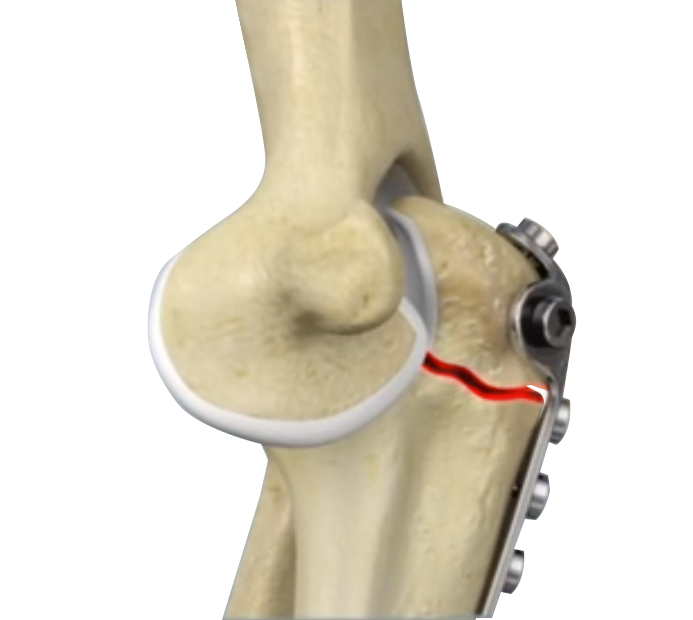

ORIF of the Distal Humerus Fractures

A distal humerus fracture is a condition that occurs when there is a break in the lower end of the humerus bone that commonly occurs as a result of severe trauma.

ORIF of the Humerus Fractures

Open reduction and internal fixation (ORIF) of humerus fractures is a surgical technique employed for the treatment of humerus fractures to restore normal anatomy and improve range of motion and function.